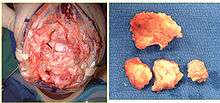

Articular surface

The articular joint's surface must be smooth for it to function properly. Irregularity may result in radiocarpal arthritis, pain, and stiffness. More than 1 mm of incongruity places the patient at a high risk for post-traumatic arthritis. Significant articular incongruity typically occurs in young patients after high energy injuries (Figure 2). If the surface is very irregular and cannot be reconstructed, then the only option may be a fusion.

Natural history

Nonunion is rare; almost all of these fractures heal. However, if the fracture is unstable the deformity at the fracture site will increase and cause limitation of wrist motion and forearm rotation, pronation and supination. If the joint surface is damaged and heals with more than 1–2 mm of unevenness, the wrist joint will be prone to post-traumatic osteoarthritis (Figures 4 and 5). Displaced fractures of the ulnar styloid base associated with a distal radius fracture result in instability of the distal radioulnar joint and resulting loss of forearm rotation (Figure 6).